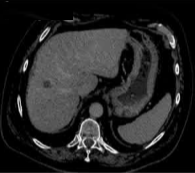

69 岁的男性患者,患有丙型肝炎相关肝硬化,其肝脏增强扫描(S8)中可见一个 22 mm 肝细胞癌结节。